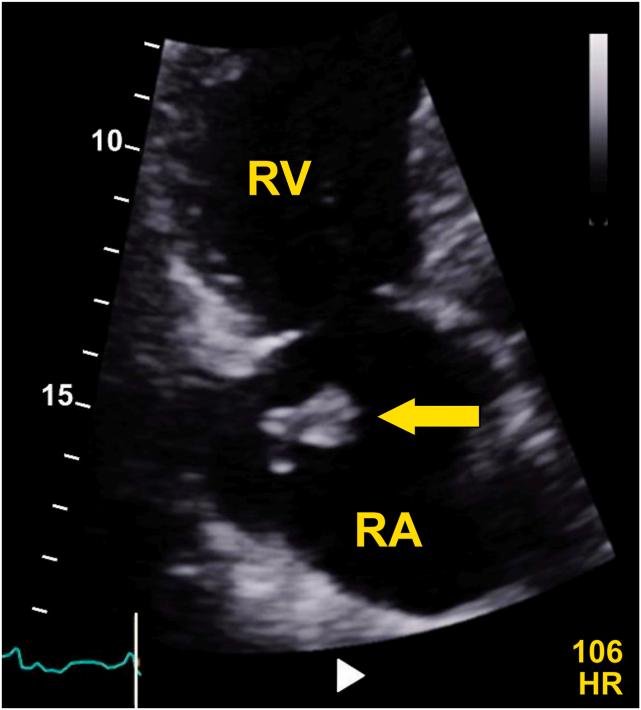

多条探索之路:超声心动图医师对动态血栓的见解——一个超声心动图病例系列

Many Roads Traveled: Sonographer Insights on Clots in Transit-An Echocardiography Case Series.

• CITs are dynamic thrombi in the heart with significant embolic risks. • Echocardiography is essential for detecting CITs and right ventricular dysfunction. • Skilled sonographers optimize imaging using advanced techniques. • Sonographers’ real-time interpretation and communication guide treatment.

摘要

• 心脏内的心脏内血栓(CITs)是具有重大栓塞风险的动态血栓。

• 超声心动图对于检测CITs和右心室功能障碍至关重要。

• 技术娴熟的超声检查人员使用先进技术优化成像。

• 超声检查人员的实时解读和沟通指导治疗。